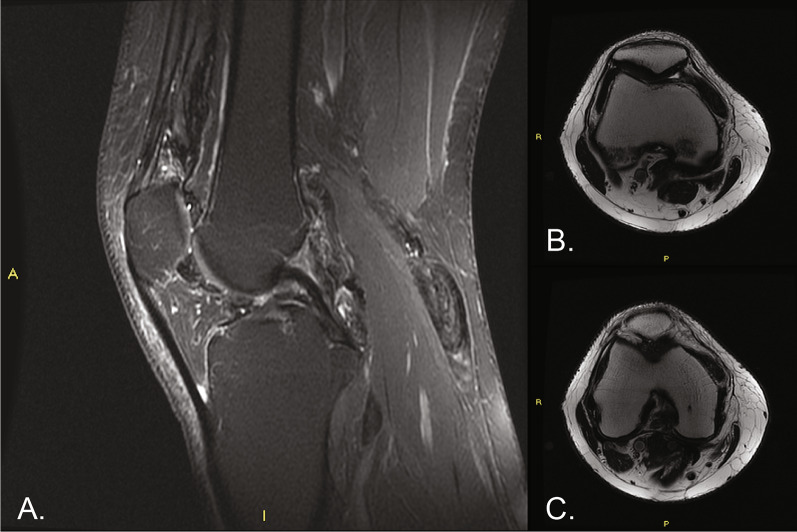

Case description: A 32-year-old man presented with intra-articular diffuse TGCT with pain and received noncurative treatment for 5 years (2014-2019). In 2019, the patient was found to have extensive disease accompanied by pain and limited range of motion. The patient's case was presented to a sarcoma multidisciplinary tumor board, who determined that surgery would cause significant morbidity and macroscopic residual tumor. As a result of the extent of disease, young age, and otherwise good health, treatment with pexidartinib was started through a compassionate use program at 800 mg/day. After dose reductions to pexidartinib at 400 mg/day and then 200 mg/day as a result of creatine phosphokinase elevations, the patient achieved a complete response after 2 years of treatment; pain was reduced and mobility was restored. The patient reported no side effects related to pexidartinib treatment. Treatment was stopped in 2022 for future family planning. After pexidartinib therapy was interrupted, the patient's wife had a successful pregnancy and delivery; however, the disease showed a slow but constant clinical deterioration, with a reduction in the range of movement of the affected knee and an apparent increase in widespread TGCT nodules.

Abstract Image